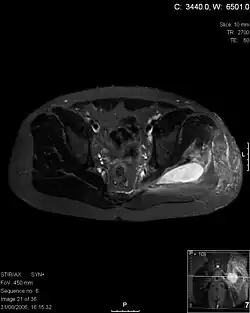

| Transverse T2 magnetic resonance imaging section through the hip region showing abscess collection in a patient with pyomyositis. | |